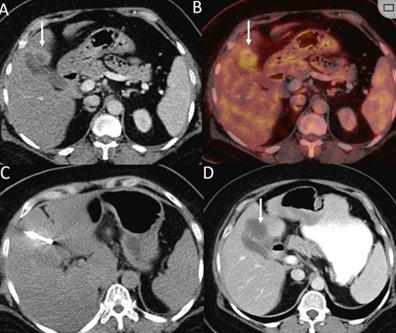

79 歲男性,肝轉移(結直腸癌)腫瘤的完全消融病例

( a ) 軸向 MRI 和 ( b ) 軸向 CT 顯示肝S8段有一個16mm的病灶,鄰近肝緣。( c )冷凍消融期間CT顯示放置了2個冷凍探針,低密度冰球包圍病灶。(d)術后1個月隨訪 CT顯示冰球?qū)膲乃绤^(qū)域,未見復發(fā)。(e)術后6個月的CT,壞死區(qū)域縮小,未見復發(fā)。(f)與基線影像(g)相比,12個月后的FDG-PET/CT顯示未見FDG攝取。

(a)軸向CT顯示病變位置毗鄰心臟和上腔靜脈(黑色箭頭)。1個月后的軸向(e)和冠狀位(f)增強CT掃描顯示低密度區(qū)域,由于肉芽組織反應引起的邊緣增強。

技術成功100%,92% 的病灶中觀察到腫瘤完全消融。16 名患者 (33%) 出現(xiàn)局部復發(fā)。10 名患者 (20%) 因局部復發(fā)或腫瘤消融不完全而接受二次冷凍消融術。